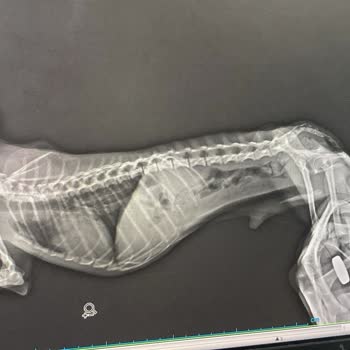

3 Mart 2026 tarihinde köpeğim Badem’i boğazında tespit edilen salya kisti nedeniyle Cerrahpaşa Veteriner Fakültesi Hayvan Hastanesi Cerrahi Polikliniği’ne ameliyat için götürdüm. Ameliyat öncesinde tarafımdan talep edilen tüm tetkikleri eksiksiz yaptırdım. Kan tahlilleri, röntgen, bt, MR ve kardiyol...